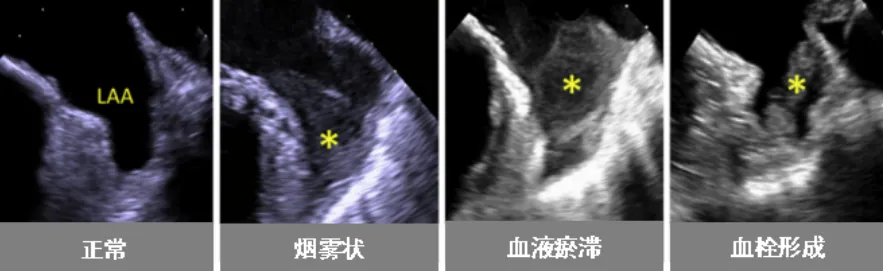

近日,老虎机app (简称老虎机app )超声医学科联合心血管内科为一名心脏病患者开展了经食管超声(TEE)检查。该项技术的开展,填补了我院在经食管超声领域的空白。患者黄阿姨(化名)今年59岁,几年前被诊断为“风湿性心脏病-二尖瓣中度狭窄”。近日,黄阿姨在医院复查心脏超声,报告提示风湿性心脏病-二尖瓣中度狭窄并中度关闭不全,且有左心耳附壁血栓形成可能(约3cm,游离端活...